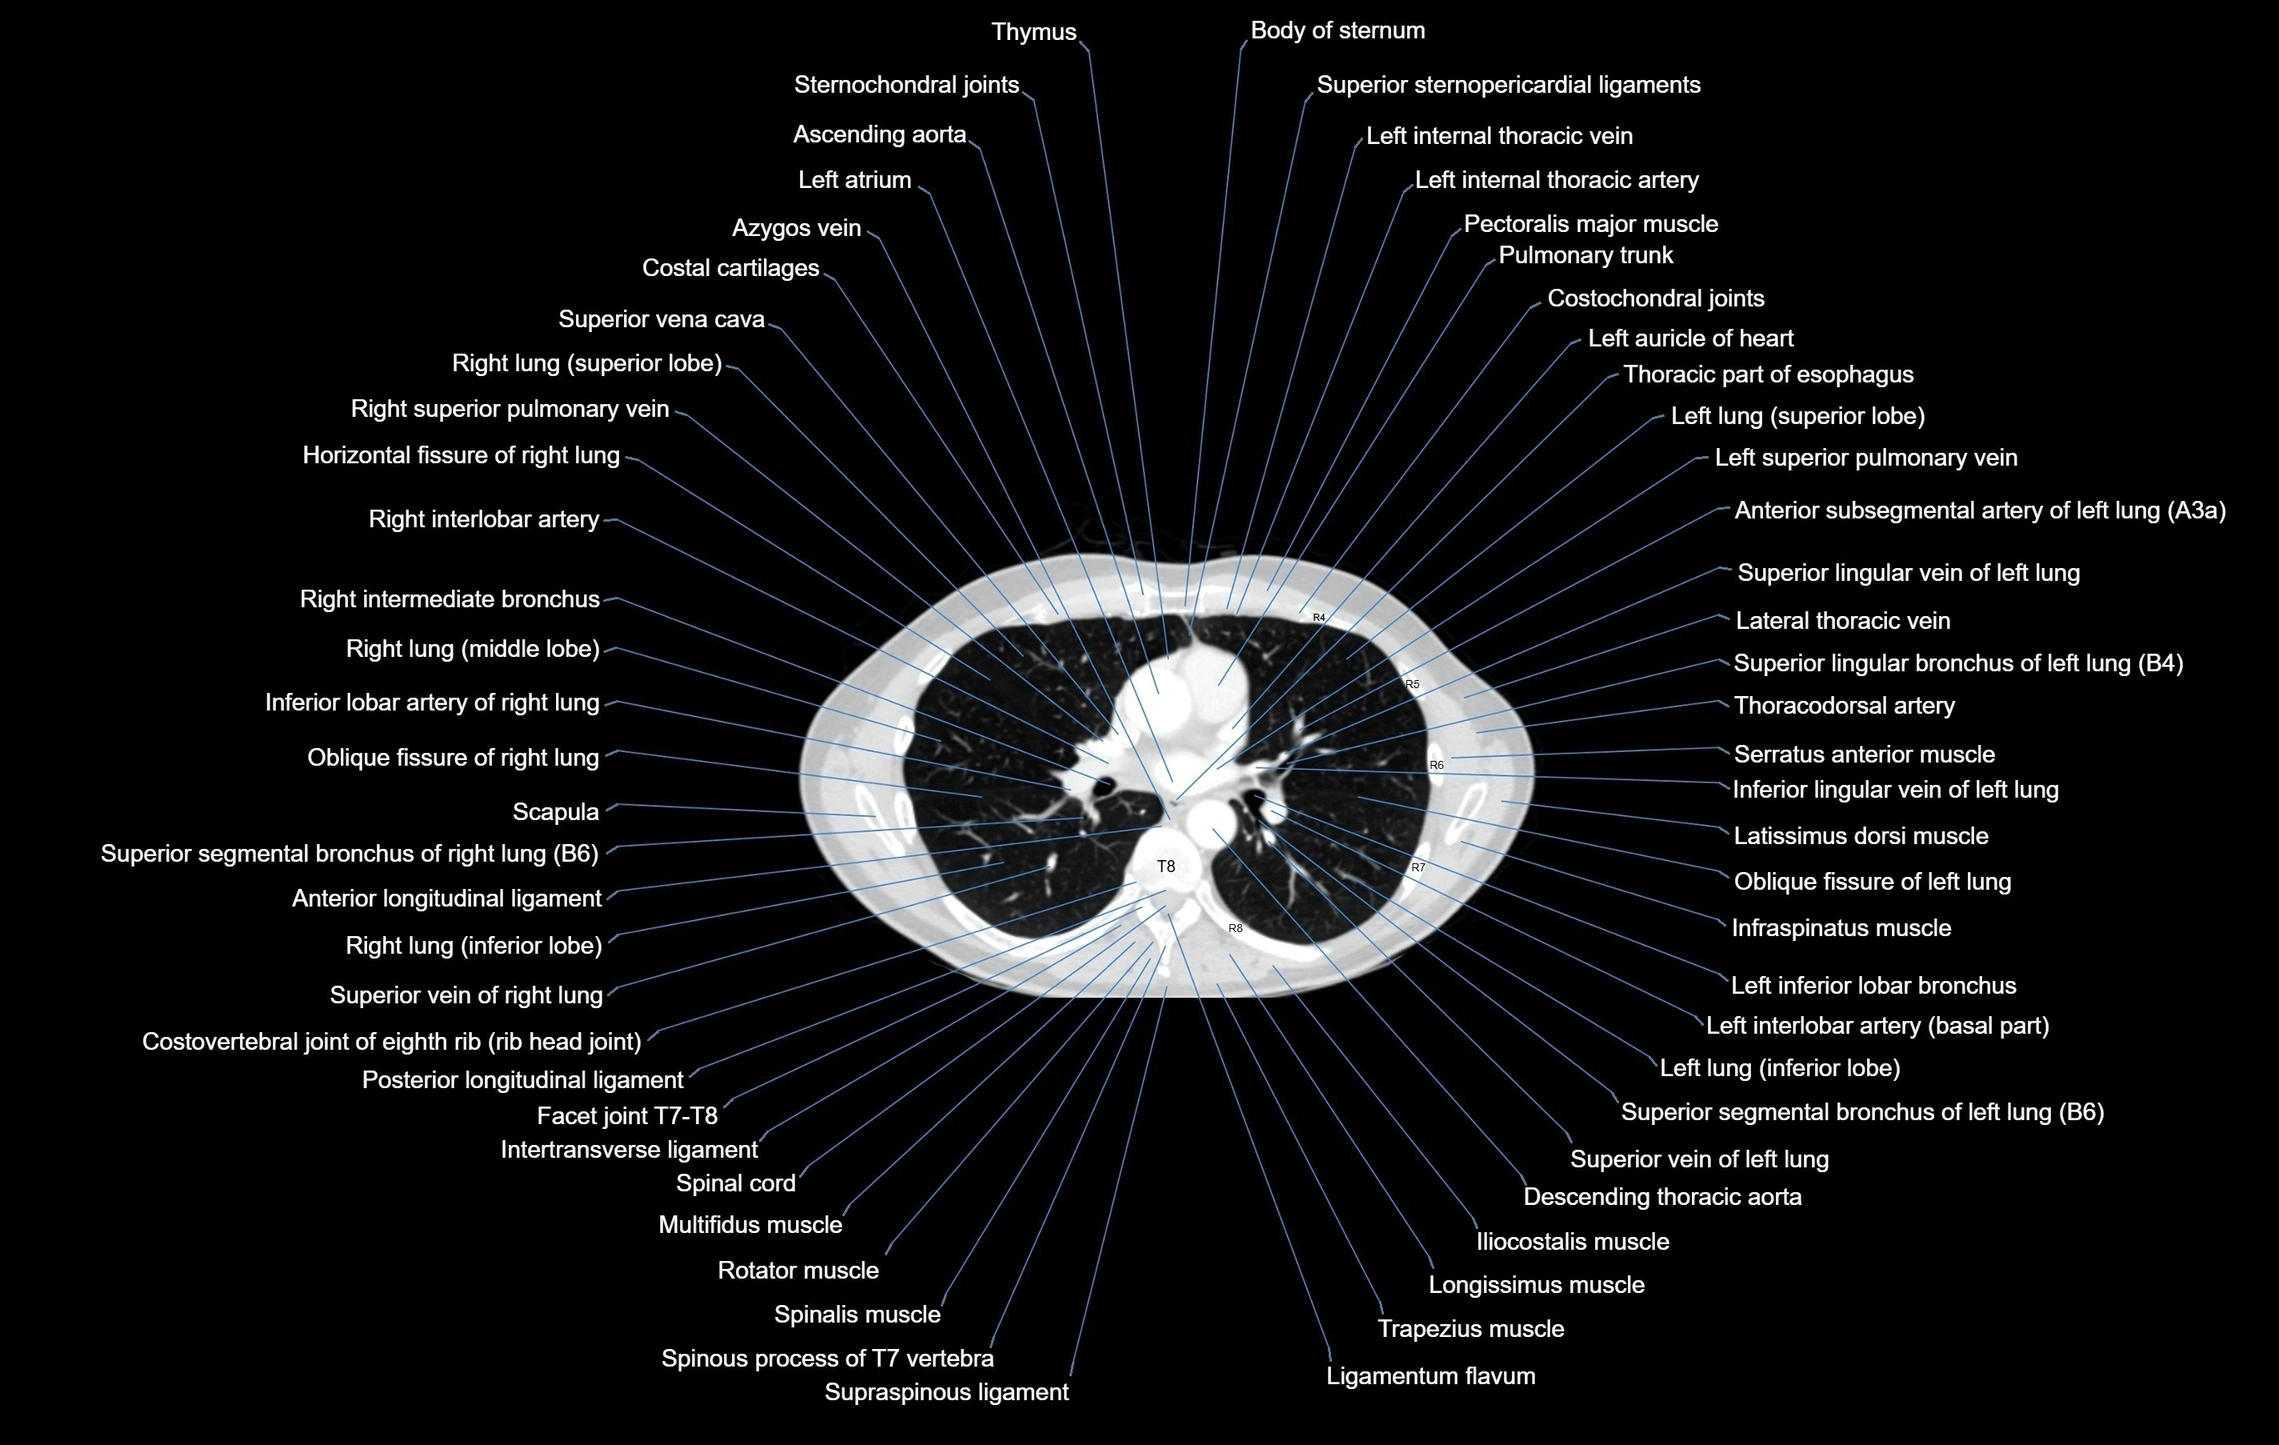

- T (Thoracic spine)